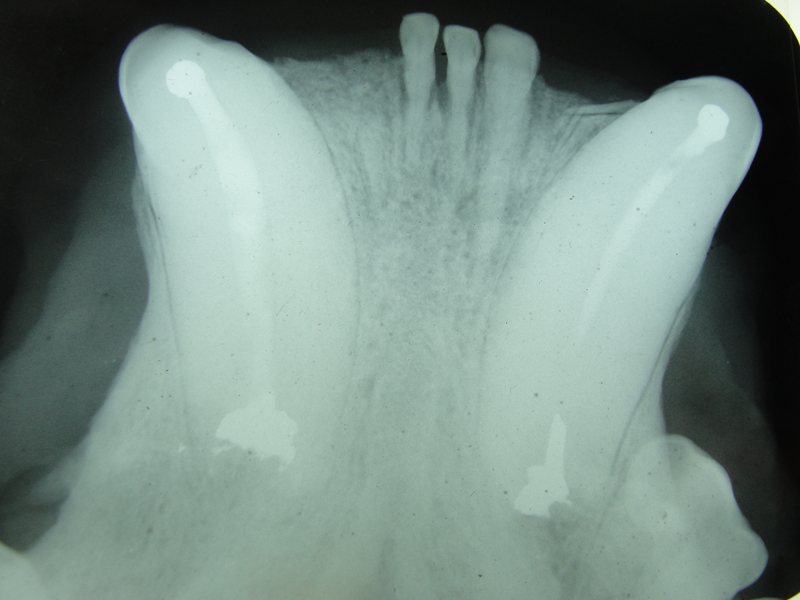

The open canal was prepared and the canal was debrided with endo files. It was irrigated with NaOCL and dried with paper points. A master cone was fitted, withdrawn and then ZOE base filler paste was deposited into the canal using the LVVES. The LVVES needle was placed at the apex and then withdrawn as the paste filled the canal. Then gutta percha was placed and condensed into the canal. When the canal was totally obturated a zinc phosphate cement base was placed over the fill. After the base set the opening was prepared with a no. 35, inverted cone bur. Then amalgam was placed and condensed.

The postoperative radiograph revealed a complete fill. Some overfill of the endo paste did flow into the chronic drainage tract.